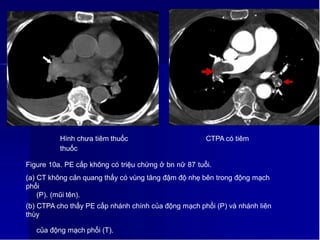

Hình chưa tiêm thuốc CTPA có tiêm

thuốc

Figure 10a. PE cấp không có triệu chứng ở bn nữ 87 tuổi.

(a) CT không cản quang thấy có vùng tăng đậm độ nhẹ bên trong động mạch

phổi

(P). (mũi tên).

(b) CTPA cho thấy PE cấp nhánh chính của động mạch phổi (P) và nhánh liên

thùy

1

3

của động mạch phổi (T).